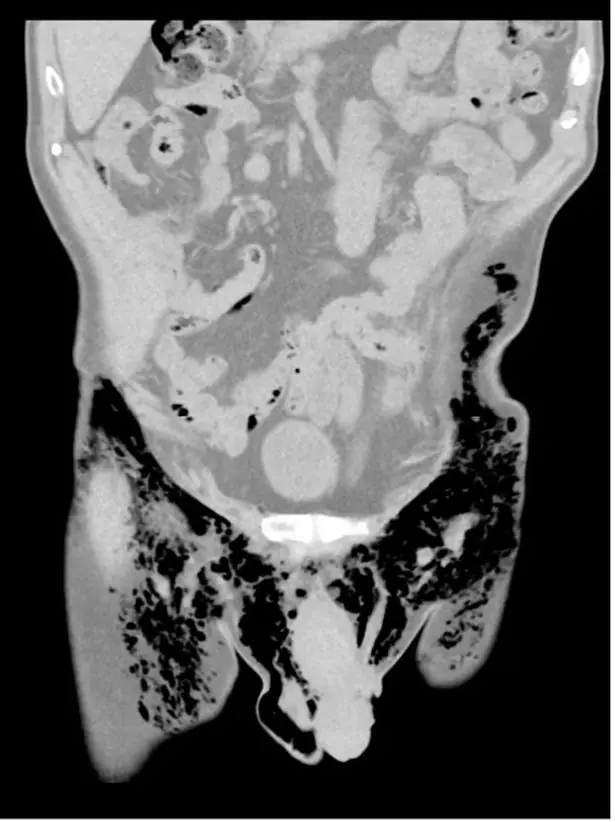

The man did, though, have air trapped in his scrotum and abdomen, a condition known as pneumoscrotum, for another two years, which was referred to as an "abnormally long time."

According to the study, the man's pneumoscrotum was potentially caused by penetrating injuries, which in turn resulted in trapped air.